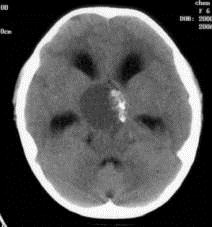

问题 病历摘要:??患者女性,6岁,半年来感觉视力模糊,近10天出现反复头痛,间有恶心呕吐,精神转差,查体:神志清楚,身高90cm,体重25Kg,血压90/55mmHg,右眼视力4.6,左眼视力4.8,双侧视乳头水肿,颈软,伸舌居中,四肢肌张力正常,肌力5级,双侧Babinski征(-)。 患者入院第三天,安排手术治疗,请选择最适用的手术入路。

选项 A.额下入路 B.翼点入路 C.终板入路 D.经胼胝体入路 E.经蝶窦入路 F.翼点-经胼胝体联合入路 G.额下-翼点联合入路 H.经脑室入路

答案 BF